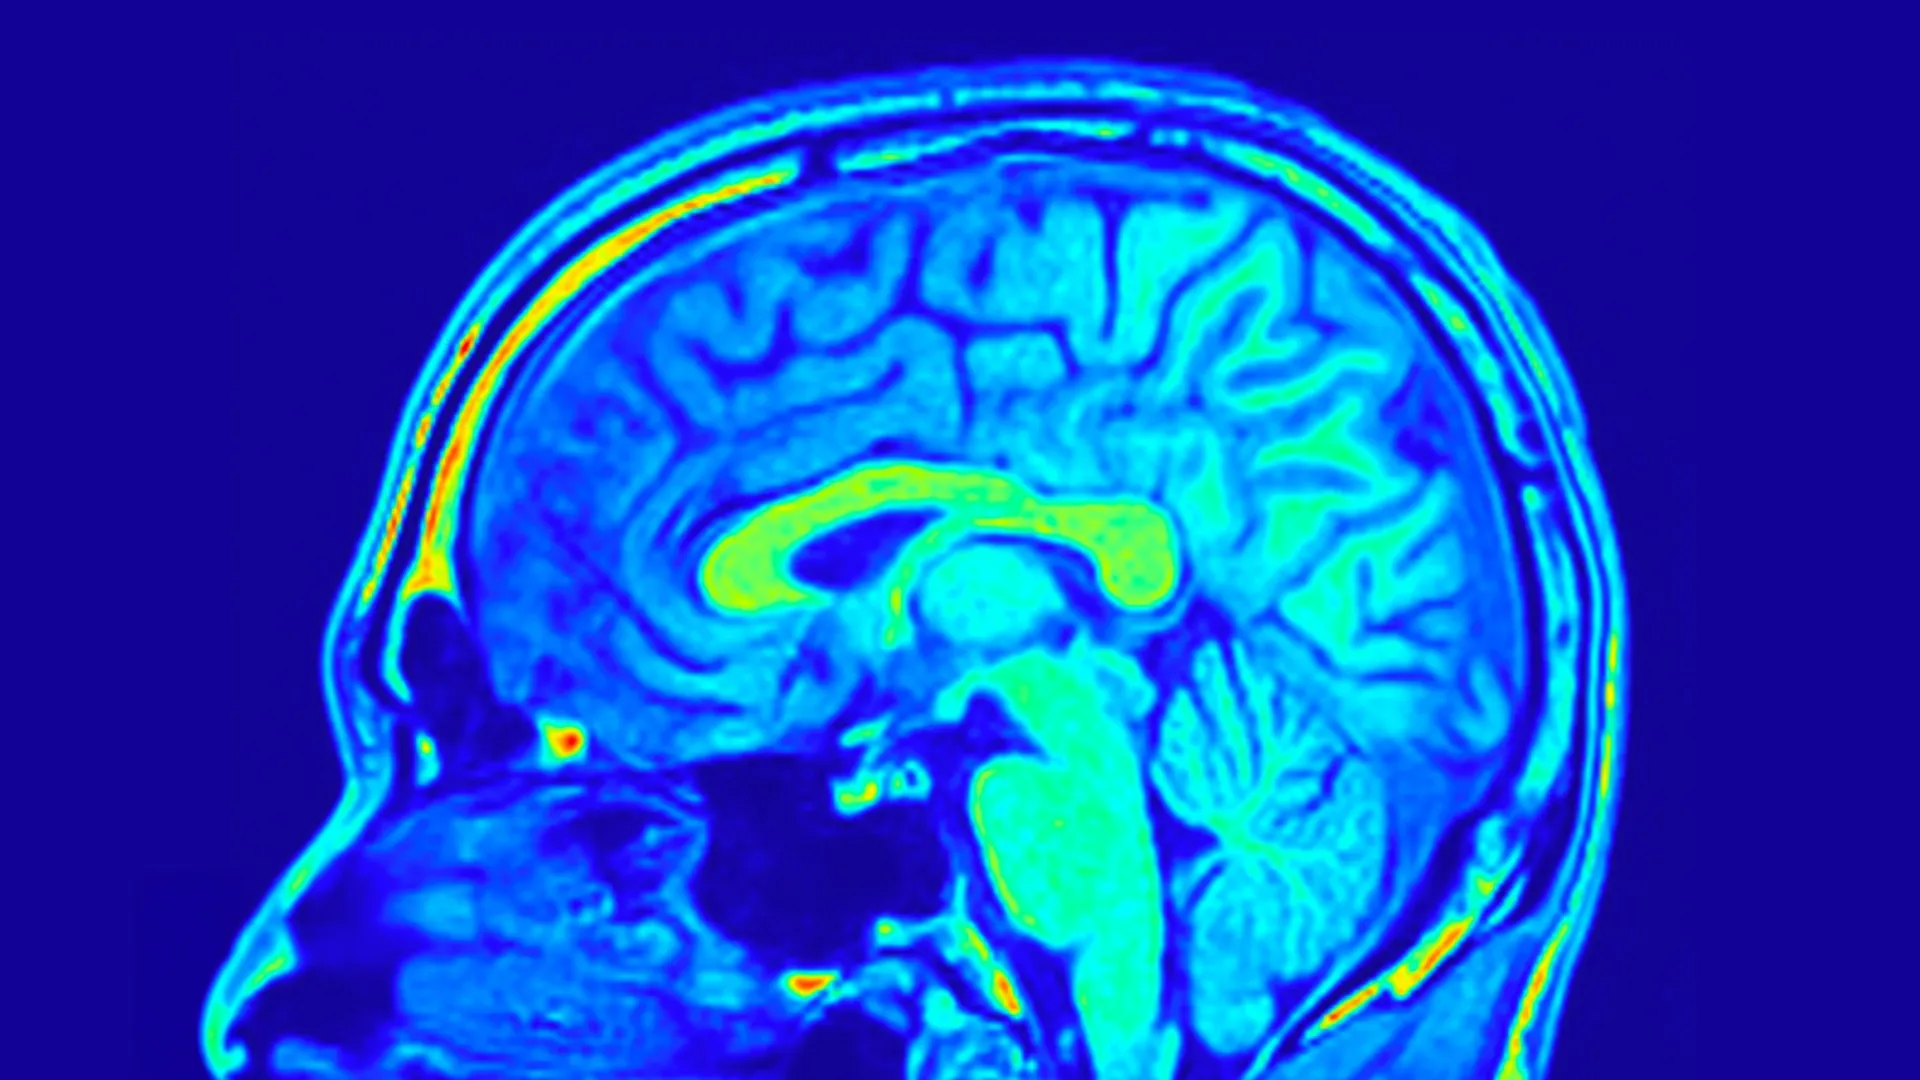

Brain scans may finally end the guesswork in depression treatment

Major depressive disorder (MDD) is a widespread and serious mental health condition that affects how people think, feel, and function in daily life. It is already a leading cause of disability, and researchers expect it to become the most common…